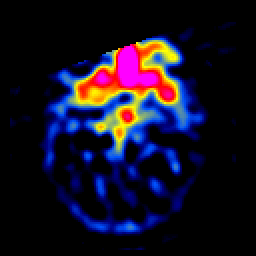

SPECT TL Study #4 -- Slice #14